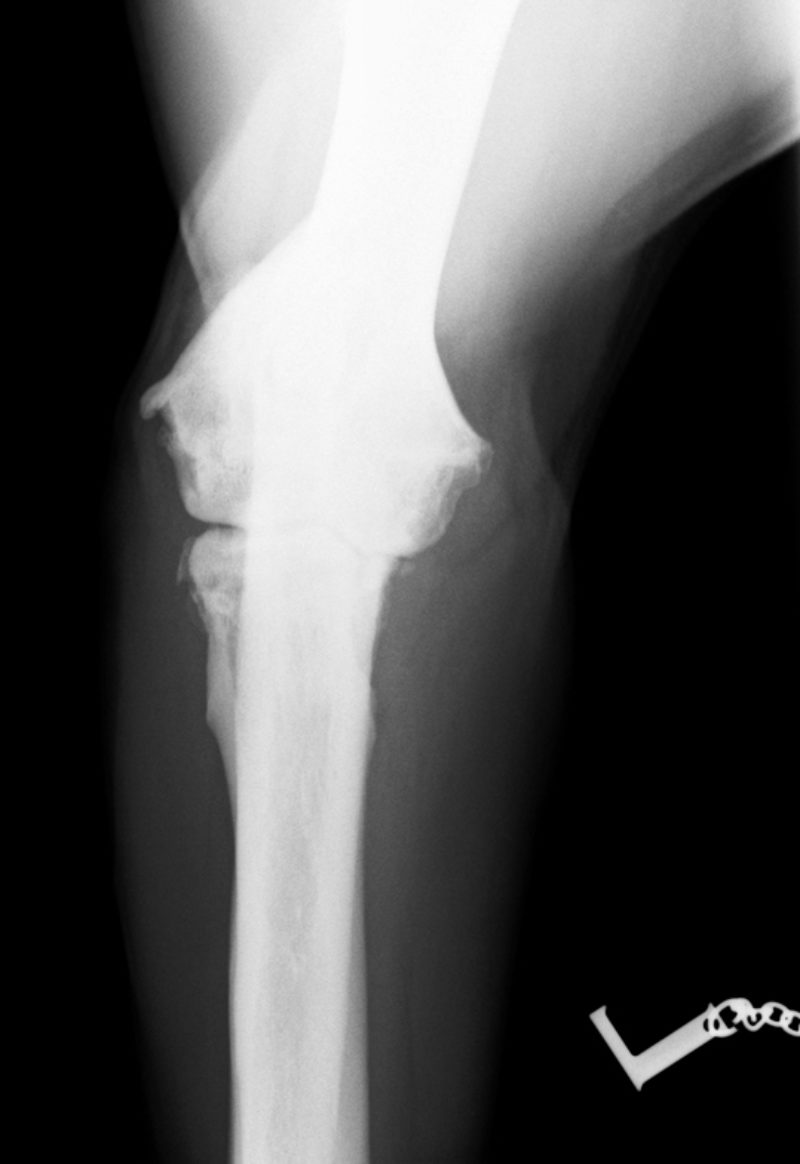

Im August 2013 wurde ein acht Jahre alter männlich kastrierter Labrador mit beidseitig hochgradiger  Ellenbogengelenksarthrose vorgestellt. Der Hund war beidseits wegen eines frakturierten Processus Coronoideus (Der Proccesus Coronoideus stellt einen wichtigen knöchernen Stabilisator des Ellenbogengelenks dar) operiert, einseitig nachoperiert und auf beiden Seiten mehrfach mit Cortison-Injektionen behandelt worden.

Der Effekt hielt etwa ein Jahr an, dann wurde die Lahmheit wieder schlimmer. Eine weitere Thrombozytenbehandlung nach 13 Monaten ergab erneut eine deutliche Verbesserung der Lahmheit für ca. acht Monate.

Insgesamt haben wir über 40 Hunde mit C-Pet behandelt, darunter war nur ein Therapieversager, bei allen anderen kam es nach Aussage der Besitzer zu einer deutlichen Verbesserung der Lahmheit. Dabei wurde von uns im überwiegenden Teil der Fälle Ellbogengelenke behandelt, dreimal ein Kniegelenk, einmal eine Hüftgelenk und einmal Zehengelenke.